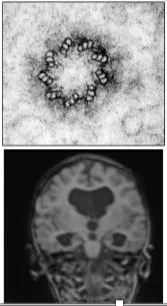

We are looking for a talented, curious and collaborative colleague who is excited about using cutting-edge technologies to join our team to develop pre-clinical models of human ciliopathies. Their project will investigate molecular mechanisms underlying disease progression, deep phenotyping across neonatal periods and establish key molecular and cellular phenotypes of disease. The post will work towards understanding reversibility of these ciliopathic disease phenotypes in different tissue settings in our pre-clinical mouse models. The post will involve liaising within the Mill team at the HGU, as well as nationally with partners across the UK, at the Mary Lyon Centre (Harwell) and Nucleic Acid Therapy Accelerator (NATA: Harwell).